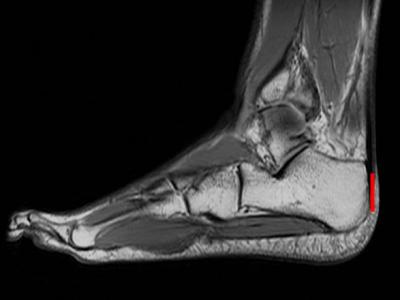

长跑运动员的脚部核磁共振图,跟骨与跟腱紧密连接,测量跟骨的长度(红线)有助于...